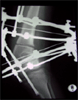

Final

Result

Good correction of Knee deformity and length restoration

Before

After